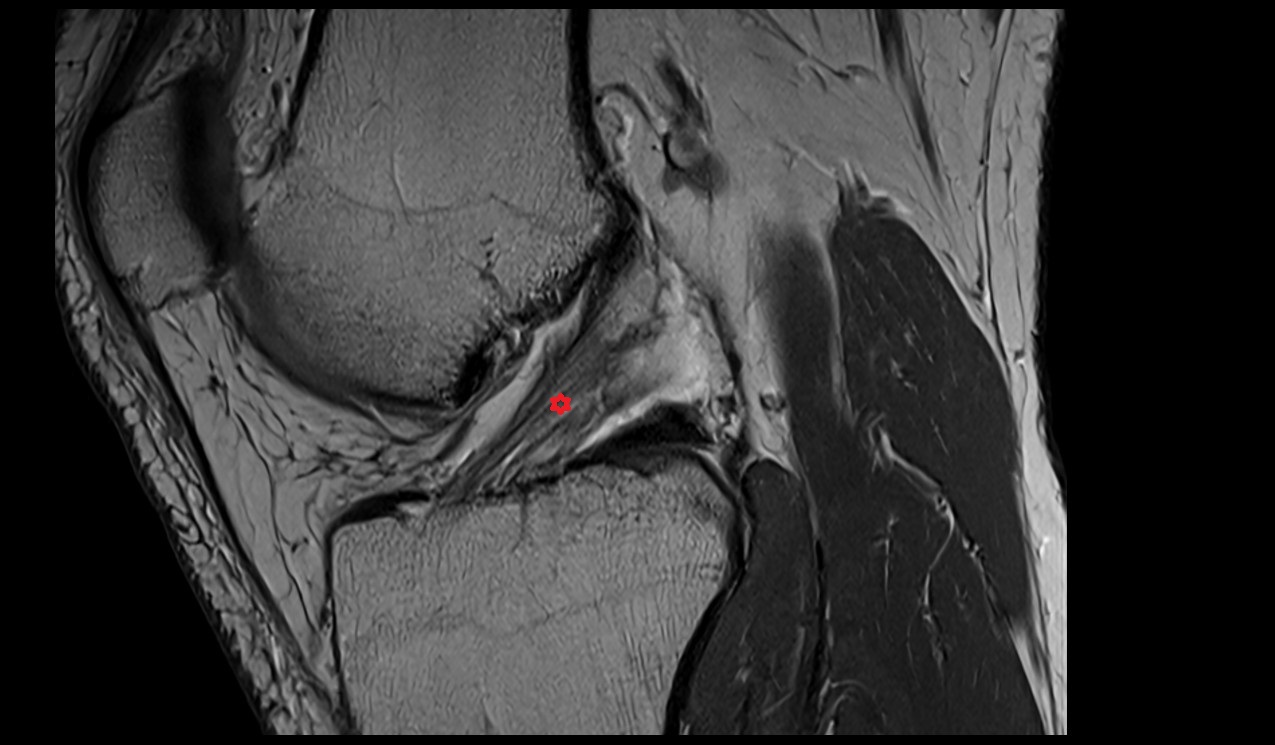

- Anterior cruciate ligament

- Posterior cruciate ligament